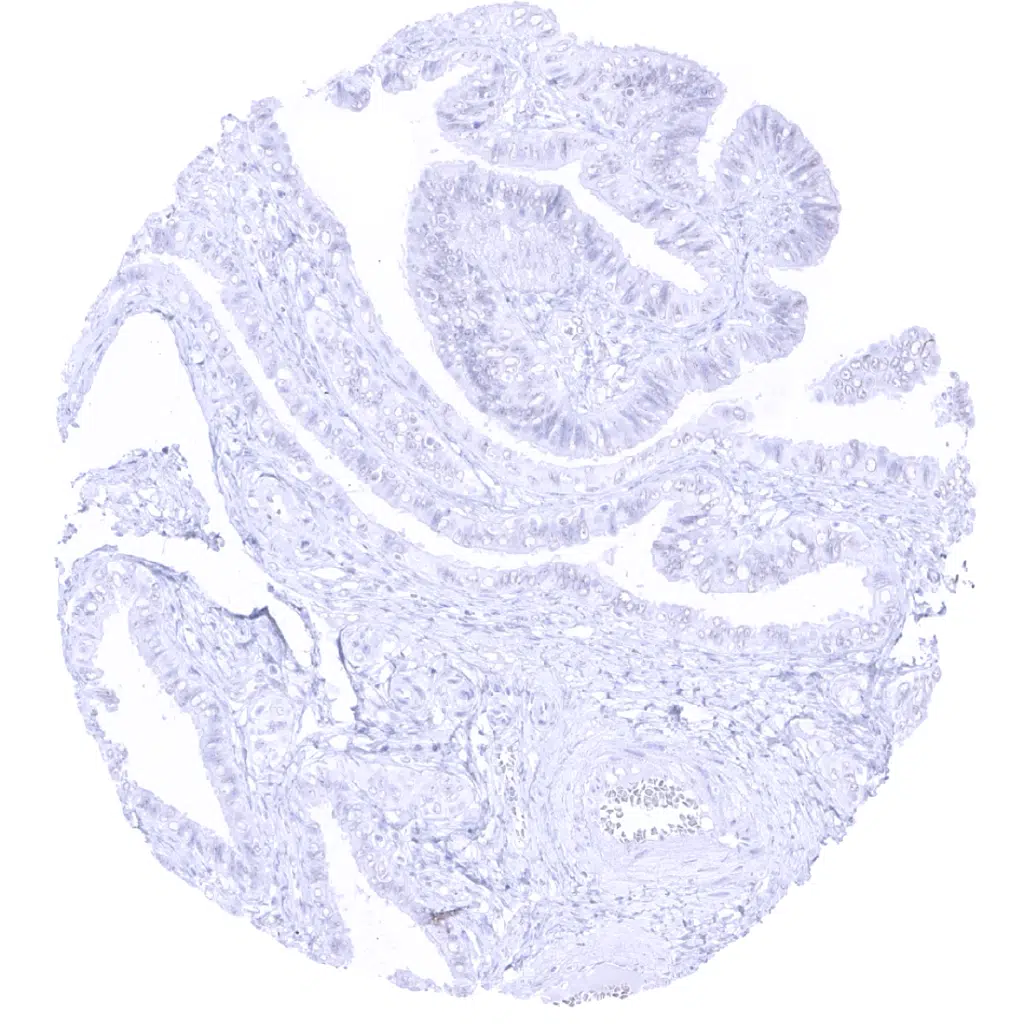

Duodenum, Brunner gland – A weak to moderate GP2 staining occurs in Brunner glands of the duodenum. The staining is cytoplasmic but shows a distinct apical predominance.